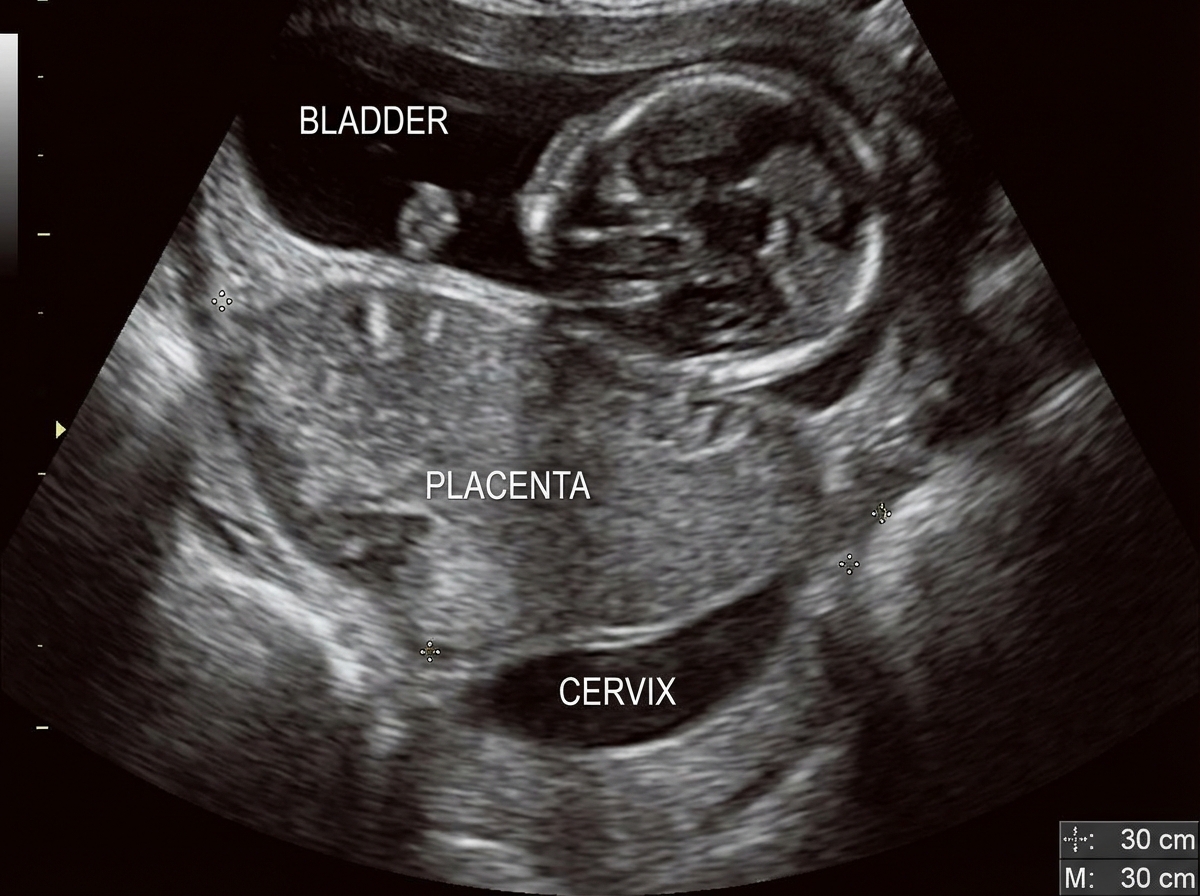

A 35-year-old multiparous lady at 30 weeks gestation presents with sudden onset painless vaginal bleeding. Ultrasound shows the following:

Explanation: ***Placenta previa*** - **Painless vaginal bleeding** at 30 weeks gestation is the classic presentation of placenta previa, where the placenta covers or lies close to the **internal cervical os**. - Ultrasound would show the **placental edge covering the internal os**, confirming the diagnosis and explaining the bleeding mechanism during cervical changes. *Abruption placenta* - Characterized by **painful vaginal bleeding** with **uterine contractions** and tenderness, unlike the painless nature described here. - Ultrasound typically shows a **retroplacental hematoma** or **placental separation**, not placental positioning over the cervical os. *Vasa previa* - Involves **fetal blood vessels** crossing the **internal os** ahead of the presenting part, causing **fetal blood loss** rather than maternal bleeding. - Diagnosed by **color Doppler ultrasound** showing vessels over the cervical os, and would present with **fetal distress** and **sinusoidal fetal heart rate pattern**. *Sub-amniotic cyst* - Represents an **incidental finding** of a small cyst within the **amniotic cavity** that does not cause vaginal bleeding. - This is a **benign condition** with no clinical significance and would not explain the acute presentation of bleeding.